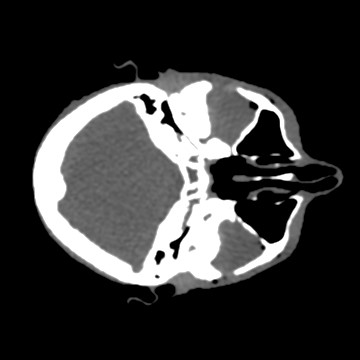

Cone-beam CT (CBCT) employs a flat-panel detector to achieve three-dimensional imaging with high spatial resolution. However, CBCT is susceptible to scatter during data acquisition, which introduces CT value bias and reduced tissue contrast in the reconstructed images, ultimately degrading diagnostic accuracy. To address this issue, we propose a deep learning-based scatter artifact correction method inspired by physical prior knowledge. Leveraging the fact that the observed point scatter probability density distribution exhibits rotational symmetry in the projection domain. The method uses Gaussian Radial Basis Functions (RBF) to model the point scatter function and embeds it into the Kolmogorov-Arnold Networks (KAN) layer, which provides efficient nonlinear mapping capabilities for learning high-dimensional scatter features. By incorporating the physical characteristics of the scattered photon distribution together with the complex function mapping capacity of KAN, the model improves its ability to accurately represent scatter. The effectiveness of the method is validated through both synthetic and real-scan experiments. Experimental results show that the model can effectively correct the scatter artifacts in the reconstructed images and is superior to the current methods in terms of quantitative metrics.